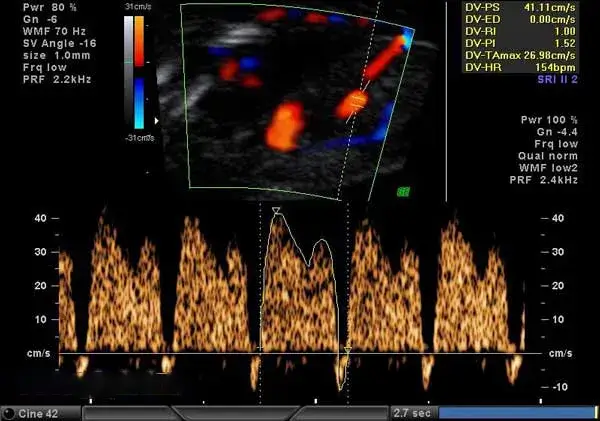

تصوير الرنين المغناطيسي للقلب في مصر:

تقع صحة القلب في قلب الرعاية الصحية، ولهذا السبب يُستخدم تصوير الرنين المغناطيسي للقلب لتقييم وتحليل صحة القلب والأوعية الدموية. يُقدم مركز الشروق للاشعة والتحاليل خدمات تصوير الرنين المغناطيسي للقلب باستخدام أحدث أجهزة التصوير لضمان الدقة والكفاءة.